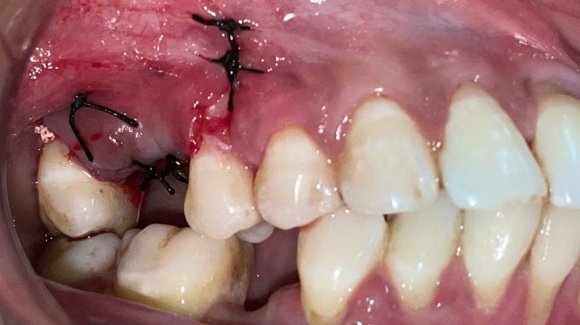

The osteotomy was then prepared into the ridge and an implant of the desired length was placed and the cover screw was tightened (Figure 3). After that, the apical portion of the implant was packed with a xenograft (Cerabone, Biotiss, Germany). The bony window, that was cut out, was placed back in the position and was covered with a PRFmembrane. Primary closure of the soft tissue was obtained. The flap was repositioned with a non-absorbable braided suture, first with horizontal mattress sutures, and, then with interrupted sutures to seal the crest (Figure 4). Postoperative instructions were provided to the patient (Table 1).